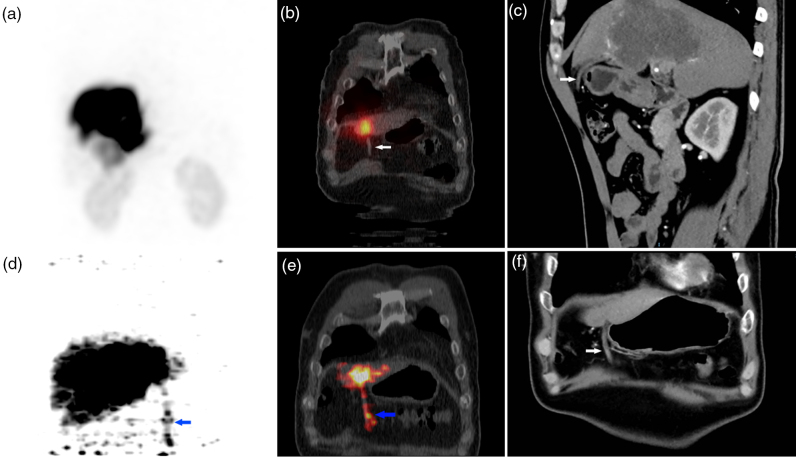

目的:探讨90Y树脂微球选择性内放射治疗(SIRT)中前腹壁(AAW)放射性示踪剂积累的差异模式,采用99mTc-MAA单光子发射计算机断层扫描(SPECT/CT)和90Y正电子发射断层扫描(PET/CT)对前腹壁(AAW)放射性示踪剂积累的影响。材料与方法:回顾性分析2022年8月至2024年11月期间接受SIRT治疗的204例不可切除肝脏恶性肿瘤患者。治疗前评估包括诊断性血管造影和99mTc-MAA成像。治疗后24小时内进行90Y-PET/CT检查微球分布。分析99mTc-MAA图像或90y微球PET/CT图像上AAW积累的患者,并以至少3个月的随访结果作为参考标准。结果:204例患者中,21例(10.3%)在99mTc-MAA图像或90y微球PET/CT图像上显示AAW积累。99mTc-MAA影像与90Y-PET/CT影像一致的有11例(11/21,52.4%),仅在90Y-PET/CT影像上有堆积的有5例(5/21,23.8%),仅在99mTc-MAA影像上有堆积的有5例(5/21,23.8%)。2例患者发现肝镰状动脉(HFA)。4例患者出现轻度腹痛,仅有1例患者出现腹部皮炎,并自行消退。其余患者在随访期间未出现任何相关副作用。结论:aaw相关的并发症罕见且轻微,提示HFA专利可能不被认为是SIRT的禁忌症;然而,99mTc-MAA和90Y-PET/CT之间的不一致强调了治疗后警惕监测的必要性,即使在治疗前没有AAW积累的病例中也是如此。

Results: Among 204 patients, 21 (10.3%) showed AAW accumulation on 99m Tc-MAA images or 90 Y-microspheres PET/CT images. Concordant findings between 99m Tc-MAA images and 90 Y-PET/CT images were observed in 11(11/21, 52.4%) cases, while five cases (5/21, 23.8%) showed accumulation only on 90 Y-PET/CT images, and the other five cases (5/21, 23.8%) showed accumulation only on 99m Tc-MAA images. The hepatic falciform artery (HFA) was found in two patients. Mild abdominal pain was observed in four patients, and only one patient experienced abdominal dermatitis, which resolved spontaneously. The remaining patients did not experience any relevant side effects during the follow-up period.